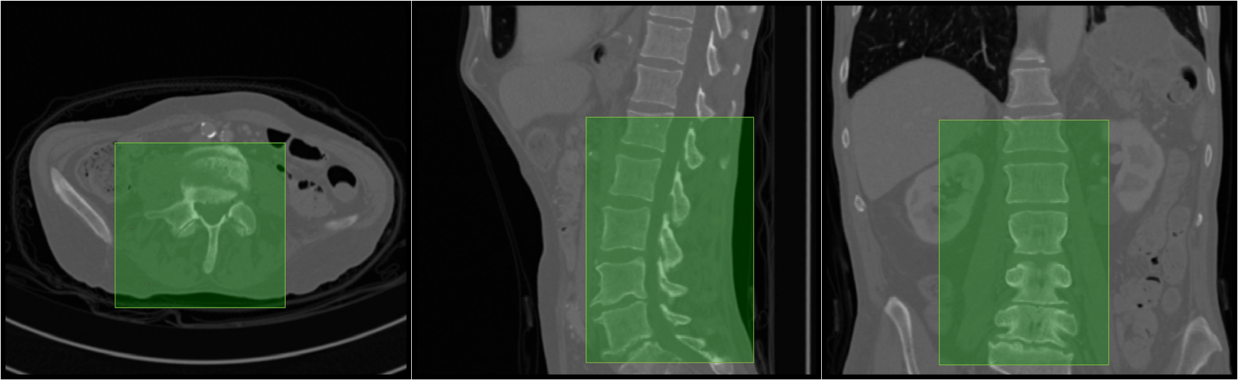

3.0.4 Discussion

In general, both the stages in our pipeline work remarkably well as per the quantitative results in tables 1 and 2. We obtain a near perfect localisation of 1.0 for almost every case, and a mean Dice score of 92%. In addition to this, the prime motivation of our approach is to successfully segment the deformed spines where the model-based approaches fail. This can be observed visually in figure 4. Four test cases as shown highlighting the highly deformed spine and vertebrae. Observe that our algorithm successfully segments these cases in spite of the severe deformations.

5.1 Additional Results

We present more results of multi-class segmentation on the test set of xVertSeg (figure 5) in addition to the results in figure 4, thereby emphasising the robustness of our approach. We also present a few aberrant segmentations analysing which could further improve our approach.